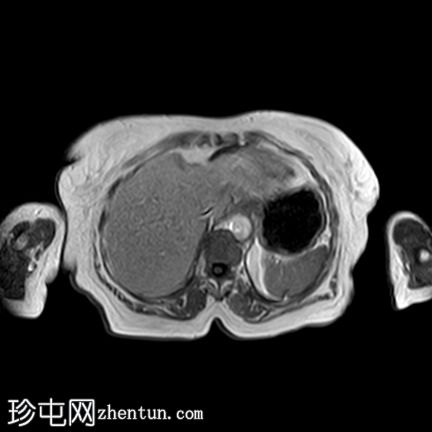

冠状位

T2

子宫呈U形,宫底轮廓消失,宫底突出至扩张的阴道内,宫颈位于内翻的宫底上方(II级子宫内翻):

宫底处可见阴道内可见边界不清、分叶状实性肿块,明显扩张阴道壁,阴道壁完整。

肿块最大轴向及头尾径约为 9.7 x 9.6 x 9.5 cm,T1 加权像呈低信号,T2 加权像呈中/高信号,伴有扩散受限和不均匀增强。

左侧附件复合体病变,包含实性和囊性成分,轴向径约为 5.3 x 4.7 cm。实性成分 T1 加权像呈低信号,T2 加权像呈中信号,伴有扩散受限和增强。

检查结果显示为 II 级子宫内翻,子宫底可见一巨大肿瘤性实性肿块,该肿块延伸并扩张了阴道,具体情况如上所述。

左侧附件复杂肿瘤性病变。